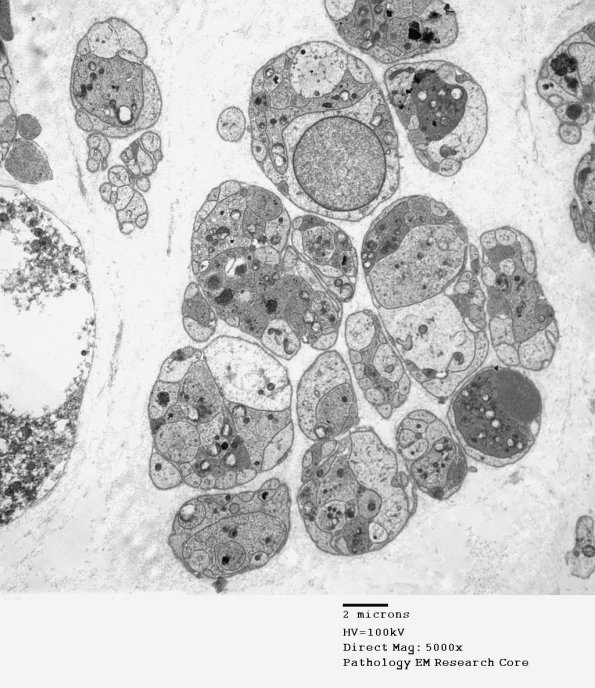

Numerous regenerative axons in Schwann cell tubes. In most cases axons and Schwann cell processes can be separated on the basis of density, shape and contents but small processes may not be separable morphologically. Schwann cell cytoplasm in this case is pale and denser processes appear to be axons. (electron micrograph)